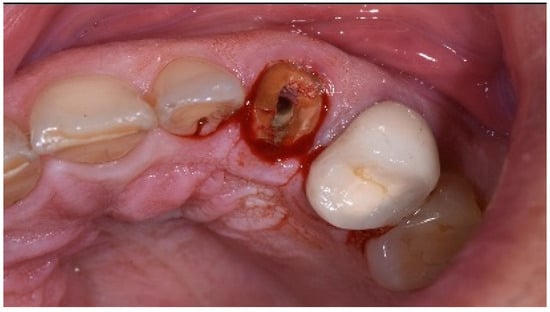

One hour before the surgical procedure, the patient received a prophylactic dose of 1 g of amoxicillin. Following local anesthesia, surgical access was obtained by raising a full-thickness aesthetic flap extending to the distal line angles of the lateral incisors. The full-thickness flap was extended 3–5 mm beyond the apical margin of the defect. The two central incisor roots were extracted, and the sockets were curetted with surgical curettes to remove all the granulation tissue (Figure 2). The sockets were assessed for the presence of a dehiscence and or fenestration. Two implants (Adin Dental Implants, Englewood, NJ, 07632, USA) were placed according to the manufacturer’s instructions (Figure 3).

Figure 2.

Clinical view immediately after extraction.